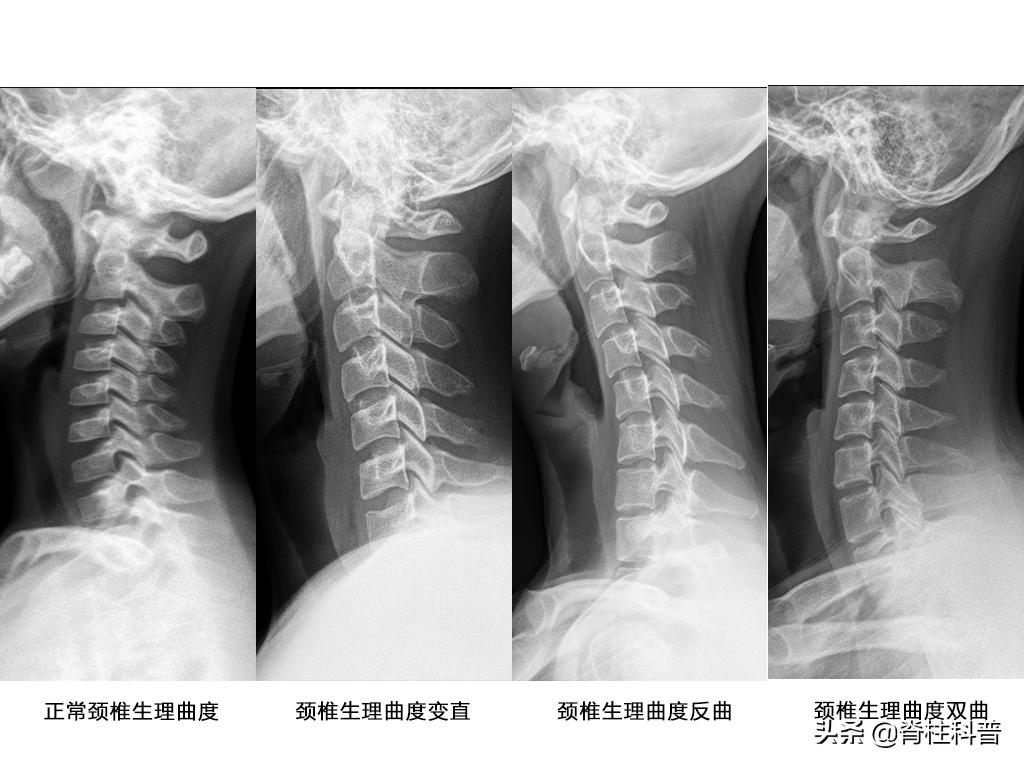

上述的情况,占脊柱外科门诊病人的多数。他们在拍完X光之后,往往会获得两个结果:颈曲度变直,或者是,颈曲度反弓。(在之前*今条头日**的推文上有讲过颈曲度变直的内容,详情请见《常见的颈椎生理弧度变直、颈椎失稳,是怎么回事?》)。

颈椎生理曲度是由椎体和前高后低的椎间盘构成的,向前凸的弧形结构,是人体适应直立行走的优化结构,有利于头颈部在三维空间进行复杂的活动,增加缓冲震荡能力、保护颅脑和脊髓。通常而言,正常的颈椎前突属于继发性弯曲,在牵拉力的作用下,脊柱弯曲变直。

正常颈部生理运动主要是靠肌肉、骨骼、韧带相互作用的,其中颈部肌肉的收缩和舒张对维持颈部活动和保持颈部正常生理曲度起着重要的作用。当颈椎姿势长期处于不良的状态中,容易导致颈部肌肉僵硬,增大颈椎局部的应变位移,影响颈椎的稳定程度,导致颈椎曲度变异。颈椎生理曲度变异的类型包括颈椎平直、反曲、双曲。